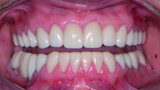

Restoring function and aesthetics with monolithic zirconia restorations